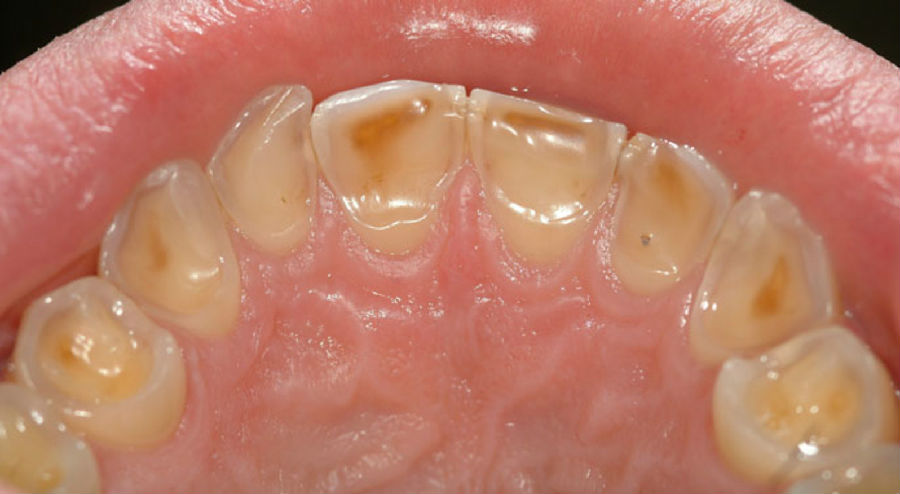

在牙侵蚀症的早期阶段,牙釉质表层会被侵蚀掉,而在后期阶段,就会使得较柔软的牙质甚至牙齿中央柔软的部分(牙髓)裸露出来。

(在牙侵蚀症的)早期阶段,牙侵蚀症会造成牙齿对冷食物敏感。如果发展下去,接下来可能会造成更严重的疼痛。并不是所有的无糖口香糖都包含食品酸味剂,通常来讲,相比其他口味的口香糖,薄荷味口香糖造成侵蚀的可能性要小些。

(牙侵蚀症)早期阶段

图片来源:作者提供

牙侵蚀症—由于酸侵蚀对牙齿造成的不可逆损伤。